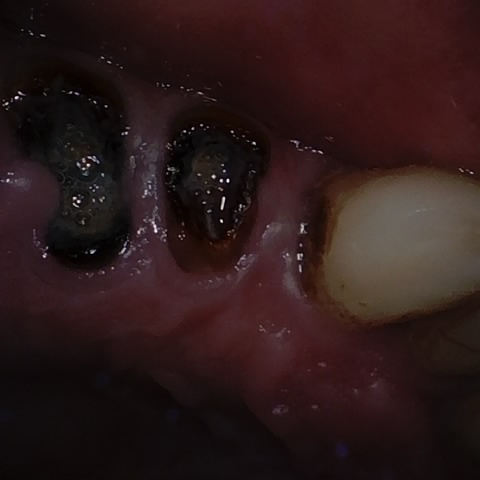

Annotated as "Good"